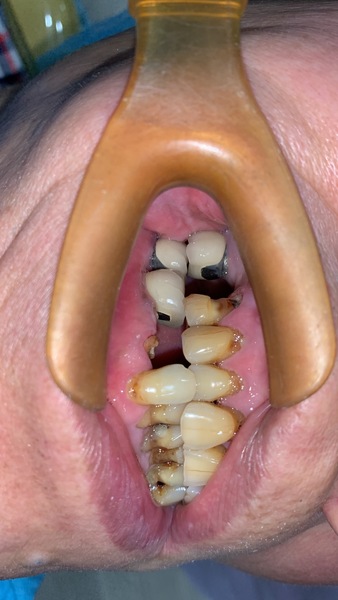

因距此位患者前一次修復牙齒已十幾年了,患者十幾年來放任牙齒不管,斷了就放著不理,或者拔牙後就不修復。

所以牙齒多處局部都受力過大,有斷裂風險。

前兩年患者認為自己身體狀況不好,決定牙齒只要壞了,就用活動假牙就可以,不想再花時間和金錢修復牙齒,太累太辛苦了。

奈何牙齒每況愈下,抽了神經後,陸續斷牙,直到累計滿5顆,真的無法再忍耐了。